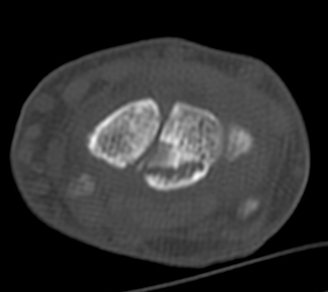

ÄÄÇ»ÅÍ ÃÔ¿µ :  ¿ù»ó°ñÀÇ ºÐ¼â°ñÀýÀÌ °üÂûµÊ(»çÁø 5, 6, 7, 8).